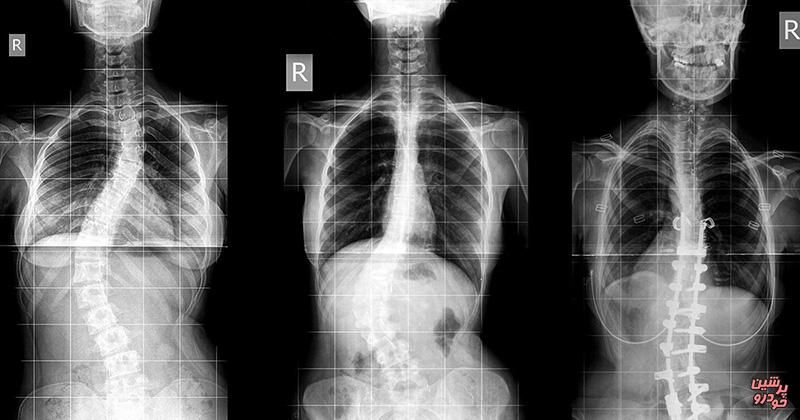

به گزارش پرشین خودرو به نقل از فارس، پس از گذشت یک دهه توسعه، نخستین اسکنر پزشکی کامل بدن در جهان، تصاویر خود را تولید کرد. این دستگاه تصویربرداری حدود 40 بار سریعتر از «برشنگاری با گسیل پوزیترون (پتاسکن)» است و میتواند تصاویر سه بعدی از داخل بدن انسان را در یک لحظه اسکن کند.

براساس گزارش «نیواطلس»، این اسکنر که «اکسپلورر EXPLORER» نامیده میشود، ترکیبی از پتاسکن و سیتی اسکن است. پس از سالها تحقیق، نمونه اولیه این اسکنر در سال 2016 ارائه و پس از آزمایشهای گسترده، در سال 2018 این اسکنر، در اندازه انسان ساخته شد.

این اسکنر جدید پیشرفتهای قابل ملاحظهای را نسبت به سیستمهای تصویربرداری امروزی ارائه میکند. همچنین آنها تصاویر کامل بدن را سریعتر و در کمتر از 20 تا 30 ثانیه میگیرند. این دستگاه به طور موثر 40 بار حساستر از سیستمهای اسکن فعلی هستند.

این بدان معناست که این اسکنر قادر است تا تصاویر با جزئیات و دقیقتری را با استفاده از دوزهای کمتری از «پرتوپییاب (تریسر)» ارائه کند. از طرفی این حساسیتهای بالا به پزشکان اجازه میدهد تا اهداف مولکولی خاصی را فراتر از محدودیت دستگاههای اسکنر فعلی به تصویر بکشند.